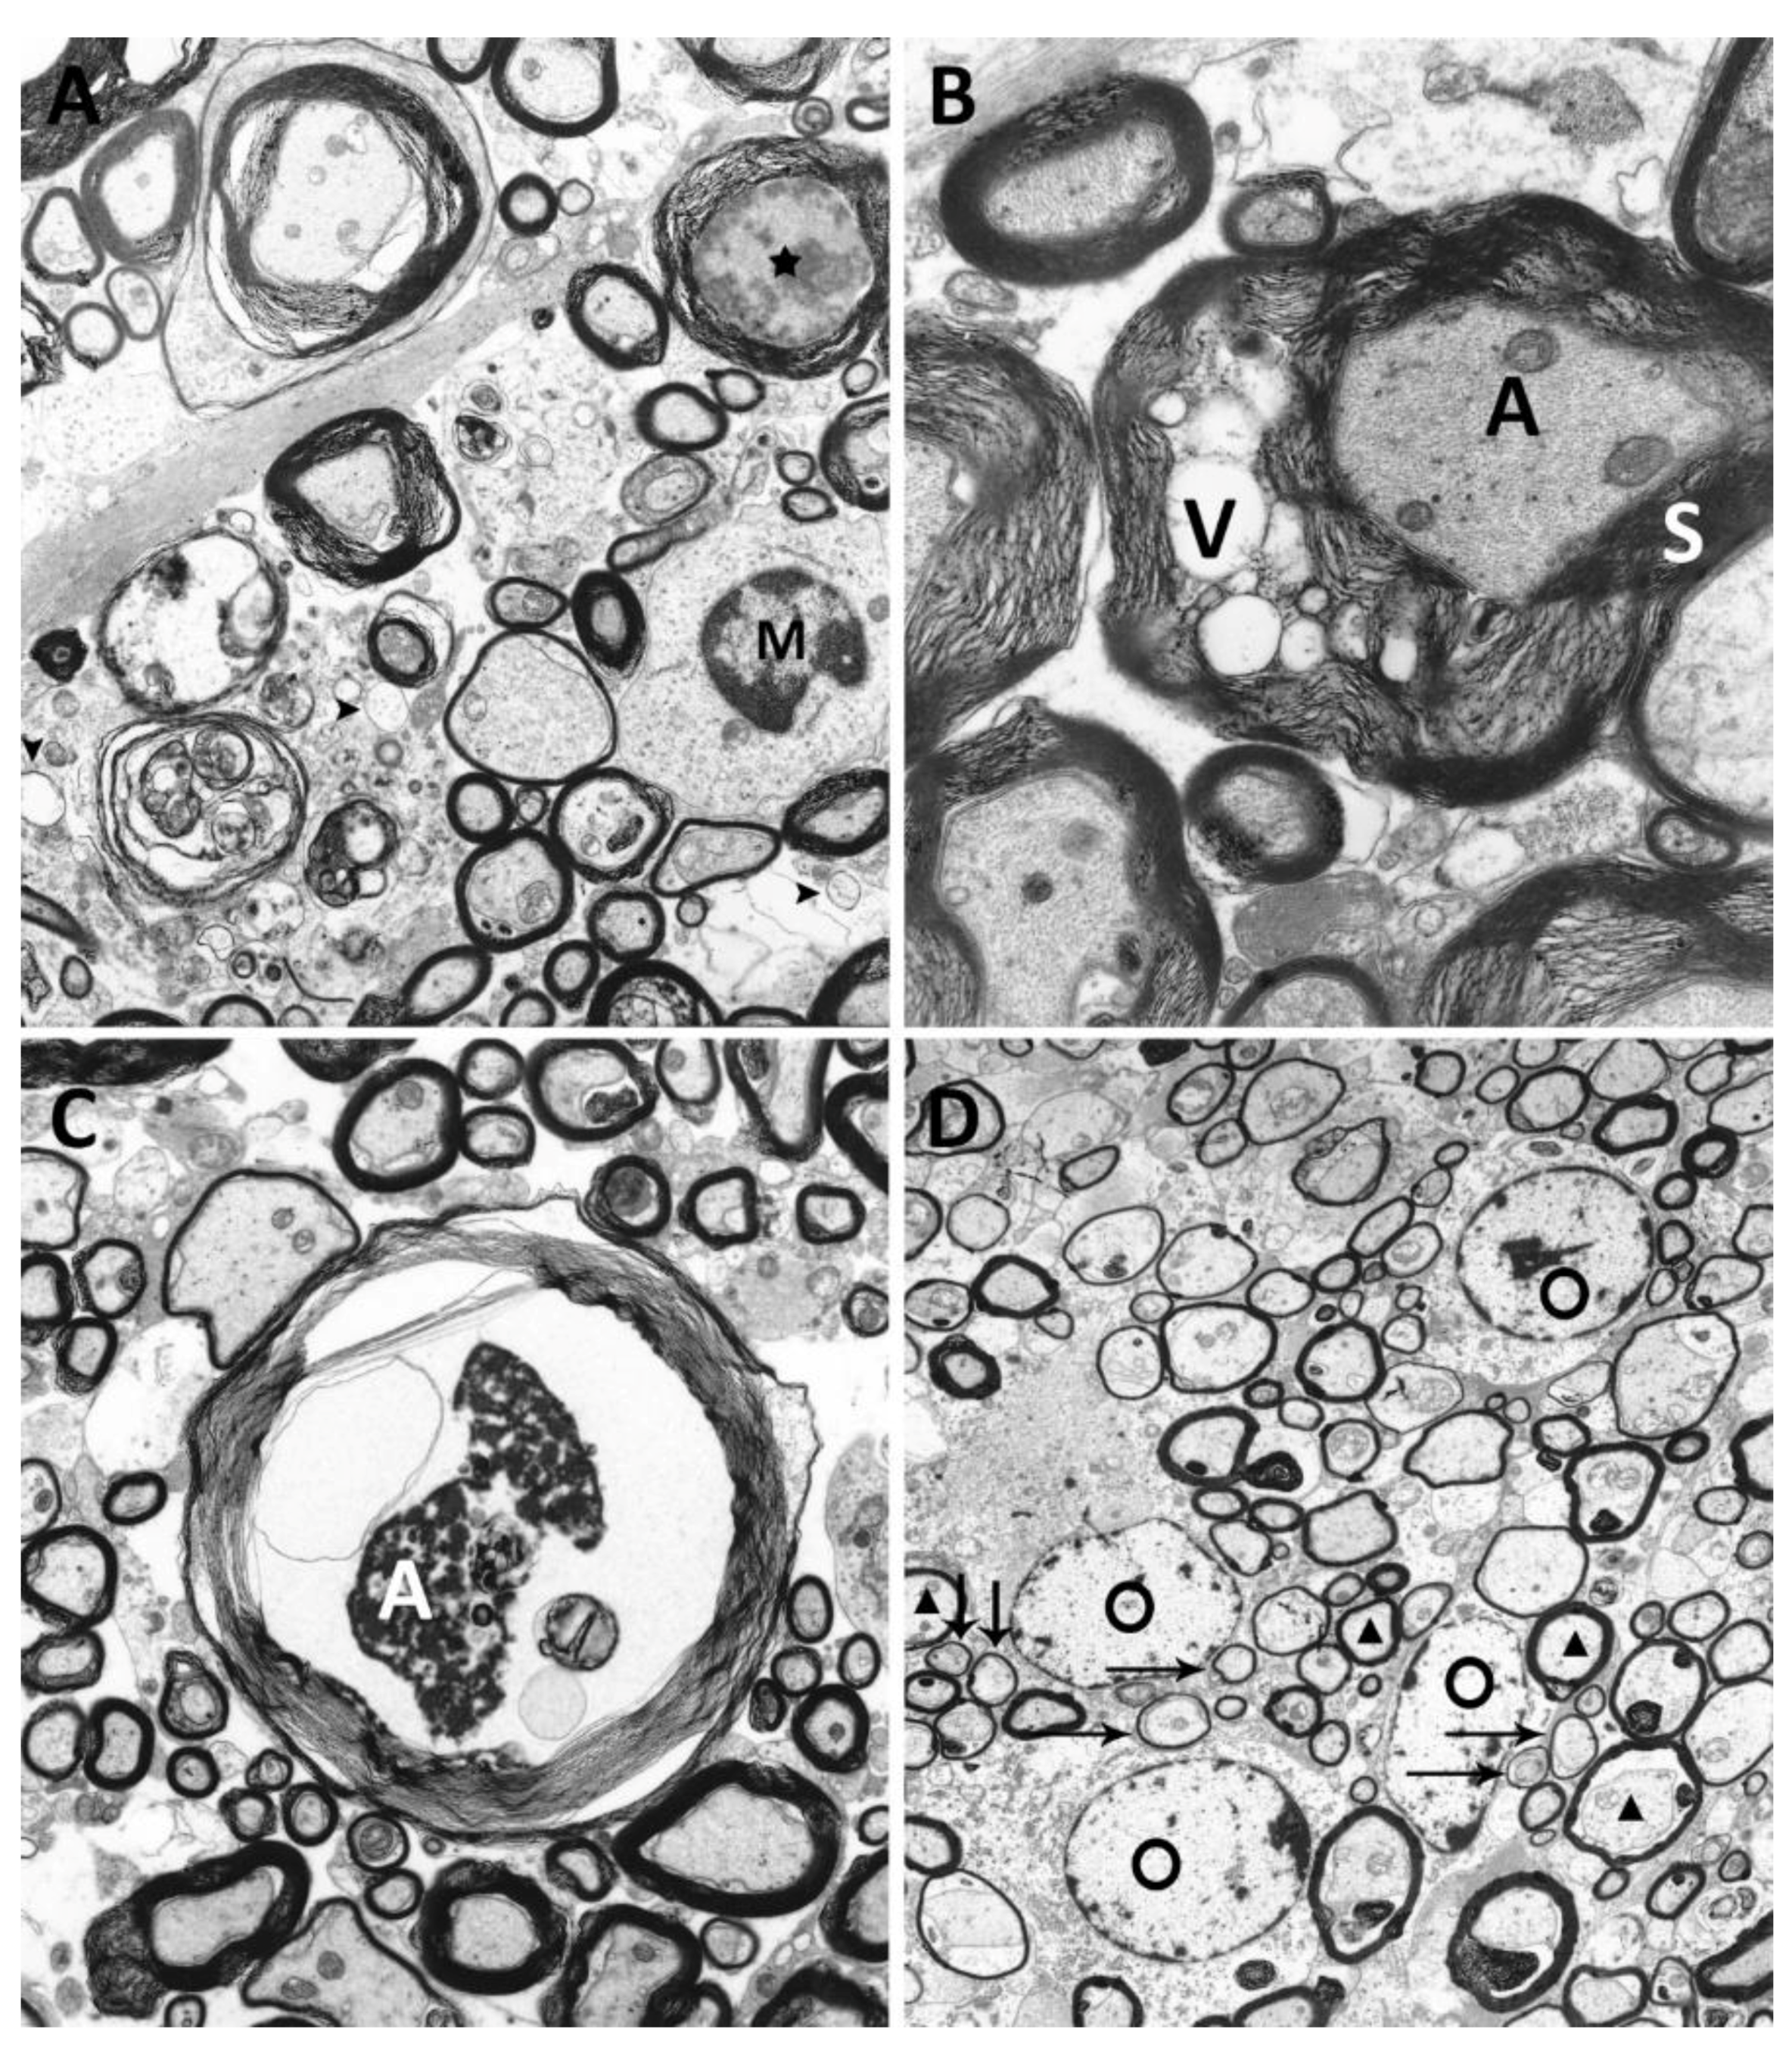

2.5. Ultrastructural Investigation of Myelin and Axons